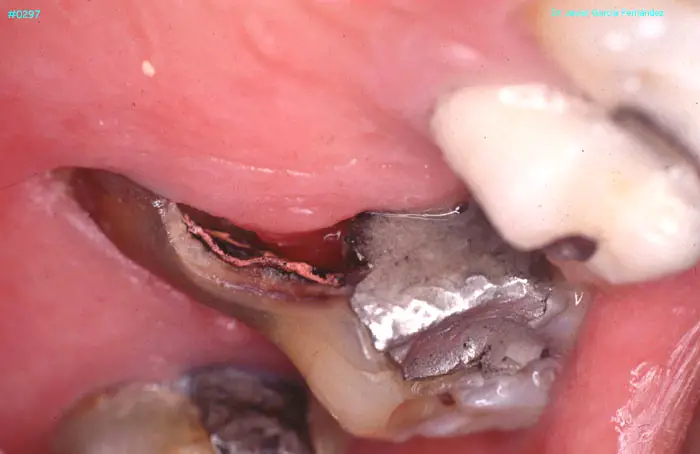

ATLAS DE CIRUGIA PERIODONTAL

image341